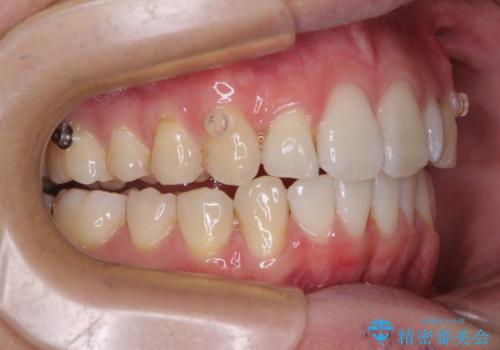

前歯のデコボコをインビザラインで綺麗に改善

- 上下前歯のデコボコとクロスバイトを気にして来院された患者様です。

インビザラインを用い、IPR(歯と歯の間を削る)と歯列全体を拡大させることで、歯並びを整えていくこととしました。

毎日22時間の装着時間を徹底してくださったのですが、左右ともに臼歯が咬合しなくなるという、インビザライン独特の症状が強く長く続いてしまい、終了するまでに長期間を要してしまいました。